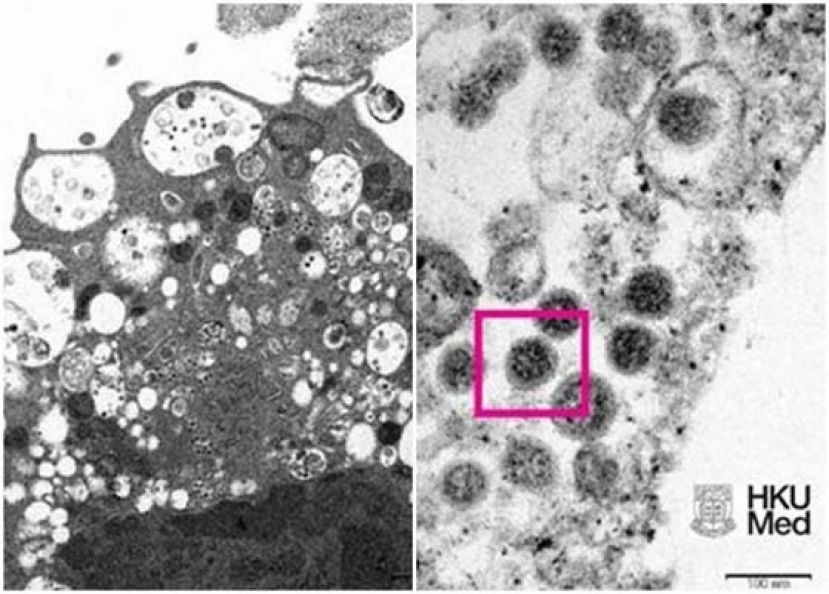

港大发布Omicron在显微镜下的真实面貌图片。 港大发布Omicron在显微镜下的真实面貌图片。

(香港9日电)新冠肺炎变种病毒Omicron在全球各地持续蔓延,香港大学医学院周三上午发布了电子显微镜下,Omicron的真实面貌图片。

在低倍电子显微镜下,感染Omicron后的猴肾细胞(Vero E6)受损,肿胀囊泡,囊泡内含有黑色小病毒颗粒。而在高倍电子显微镜下,受感染的Vero E6细胞中,病毒颗粒表面呈现皇冠形的刺突蛋白。